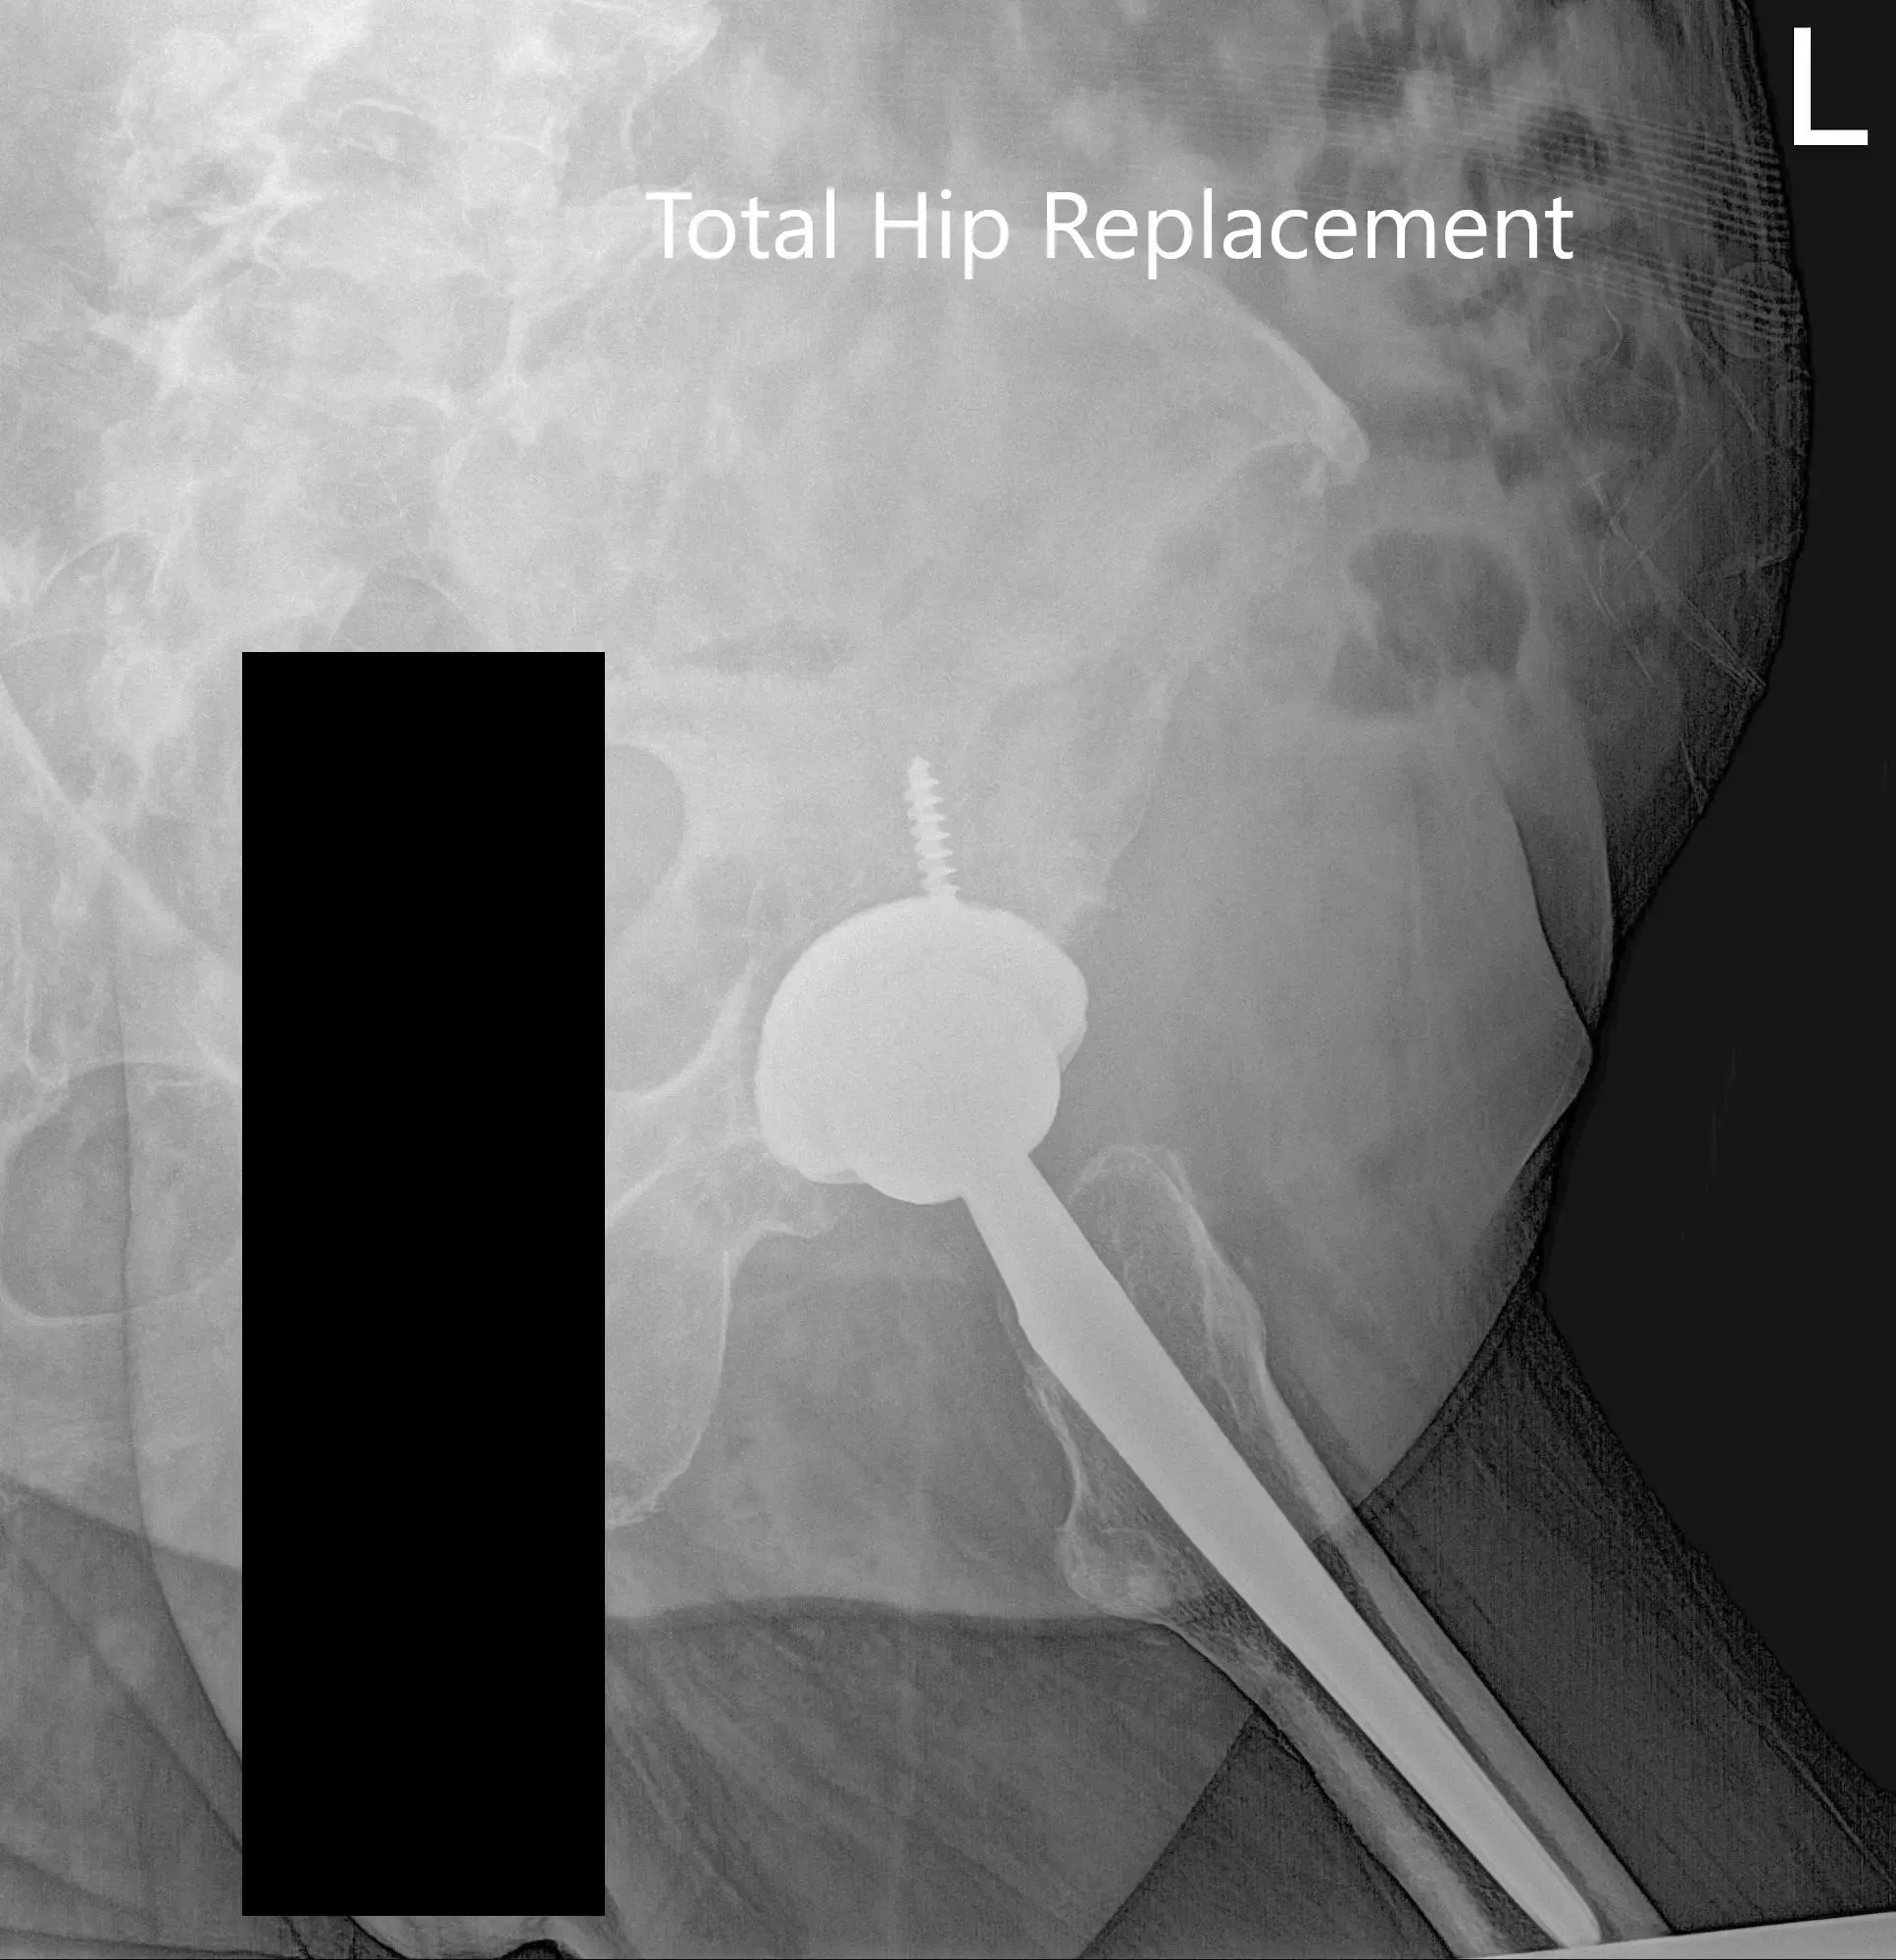

IMPLANTE UTILIZADO: Carcasa de acetábulo de 54 mm con inserto de polietileno de 0 grados, diámetro interior de 36 mm con cabeza femoral, 36 mm más 5 con tornillo de 6,5 mm x 30 mm.

Radiografía postoperatoria de la pelvis y vista lateral de la cadera izquierda.